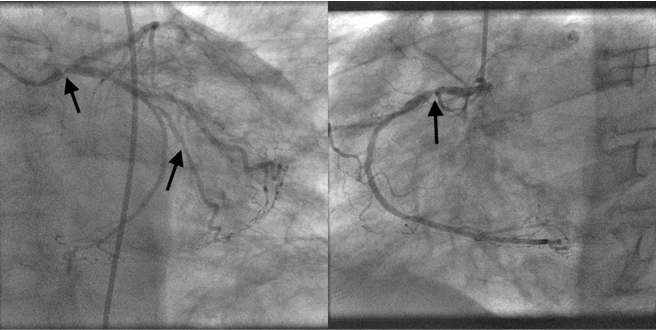

A 75-year-old male known to have Alzheimer’s disease and long-standing insulin-dependent diabetes mellitus. Present to our emergency room for three days history of altered general status, nausea and vomiting. Family state that the patient complains of a sub sternal progressive chest pain. Vital signs at presentation showed a blood pressure of 113/65 mmHg, heart rate of 98 bpm, tachypnea at 37/min. ABG showed: pH 6.9 (N 7.35-7.45), PO2 80 mmHg (N 65-105), PaCO2 19 mmHg (N 35-45), low bicarbonates 17 mEq/l (N 22-26 mEq/l), lactates 12 mmol/l. Other blood lab tests: elevated fasting blood glucose 480 mg/dl (N 72 to 99 mg/dl), normal potassium level at 3.9 mmol/l (N 3.5-5.0), elevated high sensitivity troponins at 642 ng/l, Pro BNP 2500 pg/ml, hemoglobin 12 g/dl, hepatic and renal functions were within normal limits, urine ketones were positive. The first ECG revealed large QRS complexes with a ventricular rate of 121, no ST-segment changes could be appreciated Figure 1, which is not related to potassium level changes. The diagnosis of late stage diabetic ketoacidosis was established and the patient was started on intravenous fluids and insulin. Intravenous sodium bicarbonate was also given and ECG was repeated few hours later which showed a normalization of QRS complex width, ST-segment elevation in the aVR > 2 mm, and ST depression in V3 to V6 and inferior leads. Figure 2 Transthoracic echocardiogram showed anterior, septum, apex, and inferior wall hypokinesia. The patient was taken to the Cath lab where coronary angiography showed 3-vessel disease with subtotal occlusion of left main coronary artery, second marginal and proximal right coronary artery. Figure 3 Left main and proximal right coronary arteries were stented successively with good results. Figure 4 The subsequent ECG showed complete ST segment resolution. Figure 5

Figure 3: Severe Stenosis of Left Main Coronary Artery, Second Marginal and Proximal Right Coronary Artery